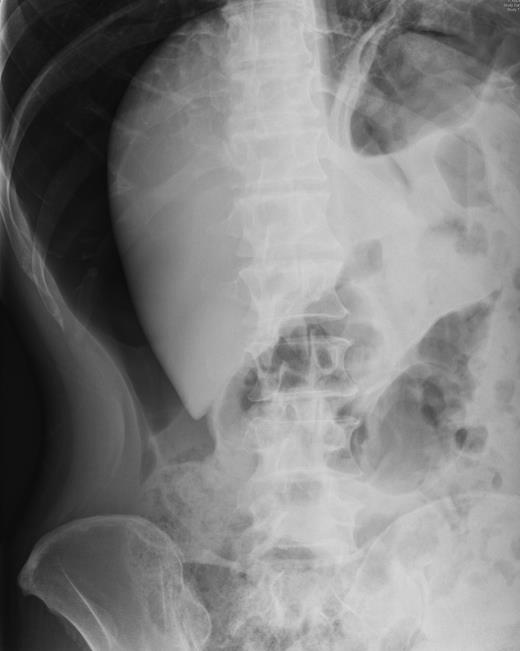

In 2011, a 46-year-old man presented with an acute abdomen. Patient had a 3 day history of abdominal pain with dyspepsia, initially epigastric with pain radiating to his shoulder. He had no associated symptoms of nausea, vomiting or change in bowel habit. There was no history of peptic ulcer disease, inflammatory bowel disease, diverticular disease or malignancy. His pain was refractory to standard analgesics and exacerbated by movement and palpation of the abdomen. There was no past medical or family history of note, and the patient had never experienced these symptoms before. Routine observations were normal, except for tachycardia. On examination, there were no peripheral stigmata of inflammatory bowel disease, abdomen was diffusely tender and tympanic, but soft with normal bowel sounds. Blood tests showed no significant abnormalities, and C-reactive protein (CRP) levels were not measured. Plain abdominal and erect chest radiographs showed pneumoperitoneum (Fig. 1) with Rigler's sign present around small bowel loops lower in the abdomen (Fig. 2).